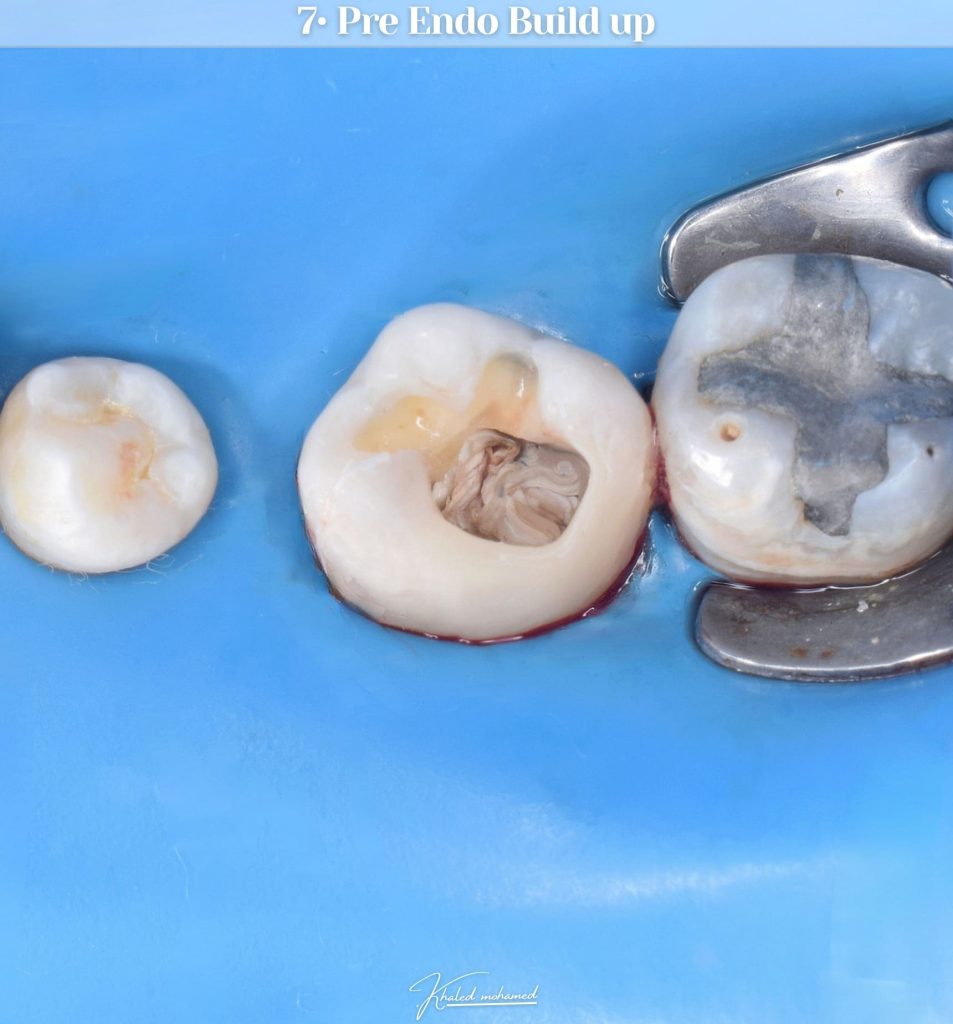

Pre endo build up

Access cavity